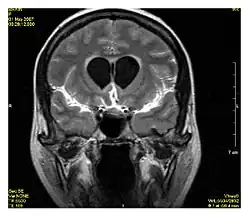

| Fluid-attenuated inversion recovery | FLAIR | Fluid suppression by setting an inversion time that nulls fluids | High signal in lacunar infarction, multiple sclerosis (MS) plaques, subarachnoid haemorrhage and meningitis (pictured).[15] |

| |